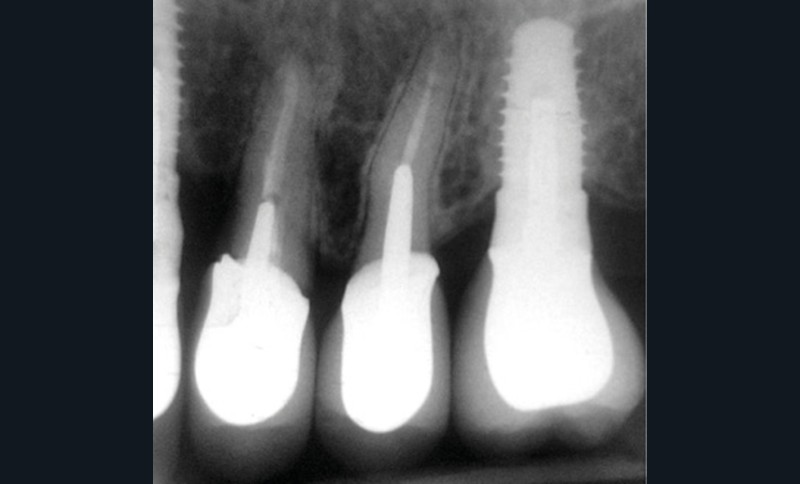

Une patiente de 64 ans, en bonne santé générale, suivie en maintenance parodontale depuis sept ans (parodontite 3B), est vue en juin 2014 pour l’extraction de sa 24 en raison d’infections endodontiques récurrentes. Le plan de traitement prévoit la pose extemporanée d’un implant et sa restauration prothétique quatre mois plus tard. La 25 est une dent couronnée et 23 et 26 sont des restaurations implantaires (fig. 1a à c). La dent antagoniste 35 est une restauration implantaire.

La radiographie péri-apicale au long cône confirme, sur la 25, un élargissement desmodontal, notamment en distal, des niveaux osseux mésio-distaux réduits par rapport aux clichés de contrôle précédents (les radiographies sont réalisées avec une technique parallèle avec des angulateurs de Rinn non personnalisés), un apex radiculaire normal et des niveaux osseux stables sur les implants adjacents (fig. 5). Le cisaillement systématique du fil dentaire lors de son passage confirme des points de contact très étroits entre 24, 25 et 26.